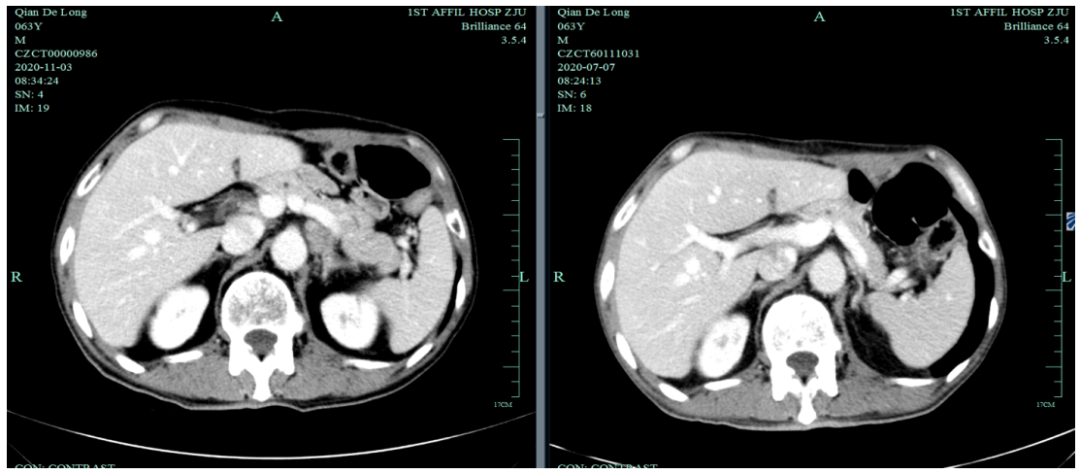

2020-11-3全腹部CT平扫+增强提示胃癌术后改变,术周及腹膜后多发肿大淋巴结显示,对照2020-7-7CT淋巴结肿大进展,结合临床疗效评估PD。